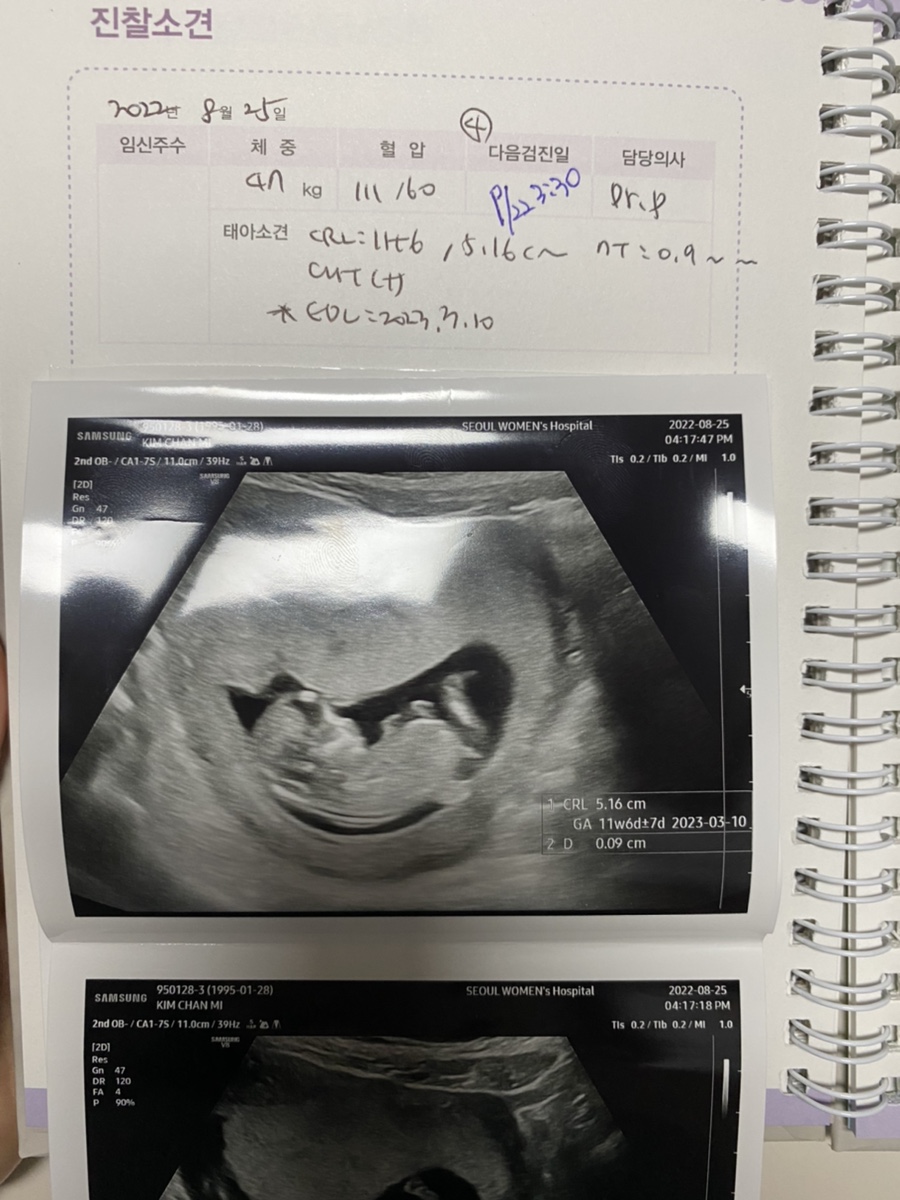

장식성장보고서(목 투명 대나무길이)

오랜만에 만난 장식은 커지고 있었다.이제 제법 얼굴 팔 다리 손 다리가 있다.

CRL(키): 5.16 나무 투명대 길이: 0.9mm 나무 투명대 길이는 기형아 선별에 중요한 자료이다.2.5~3.0mm 이하가 정상 범위이다.장식은 매우 얇아 지극히 정상적인 것으로 알려졌다.

임산부 수첩을 겨우 받았다. 대전서울여성병원은 스프링으로 되어 있어 보기 쉽다.병원에 내원할 때마다 기본 정보를 쓰고 초음파 사진을 붙여준다.